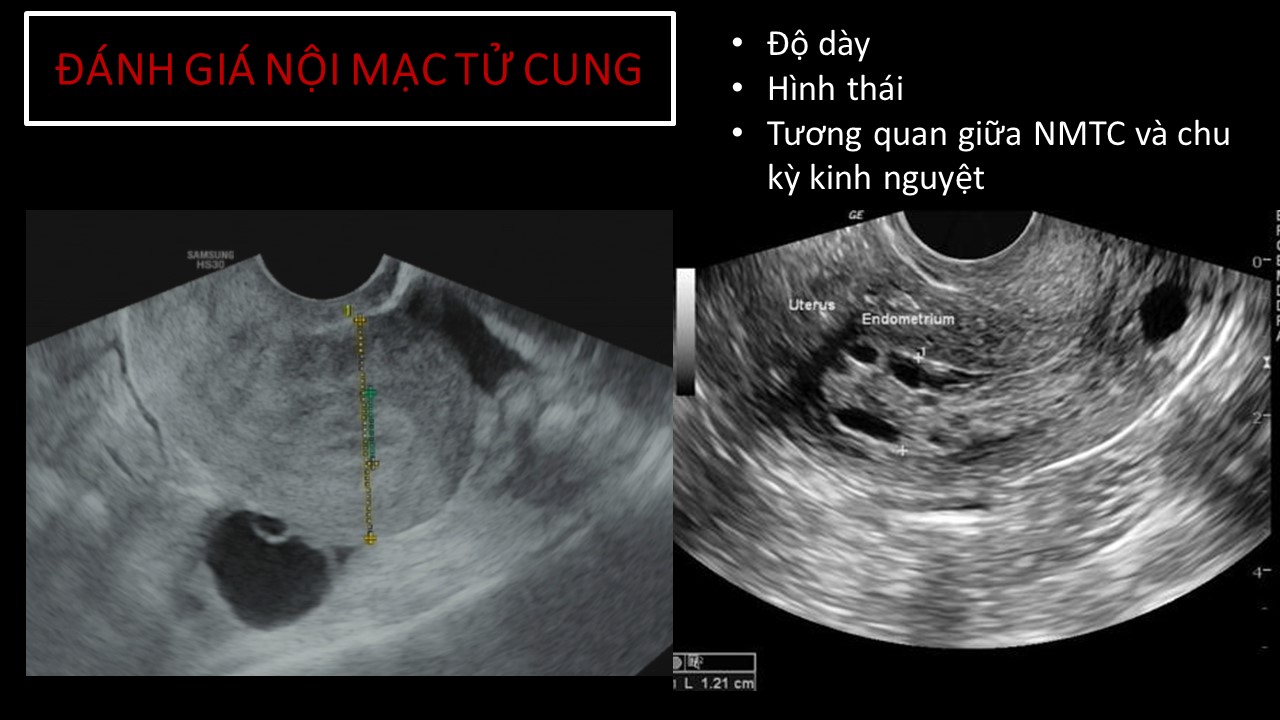

Vai trò của siêu âm trong chẩn đoán và điều trị hiếm muộn